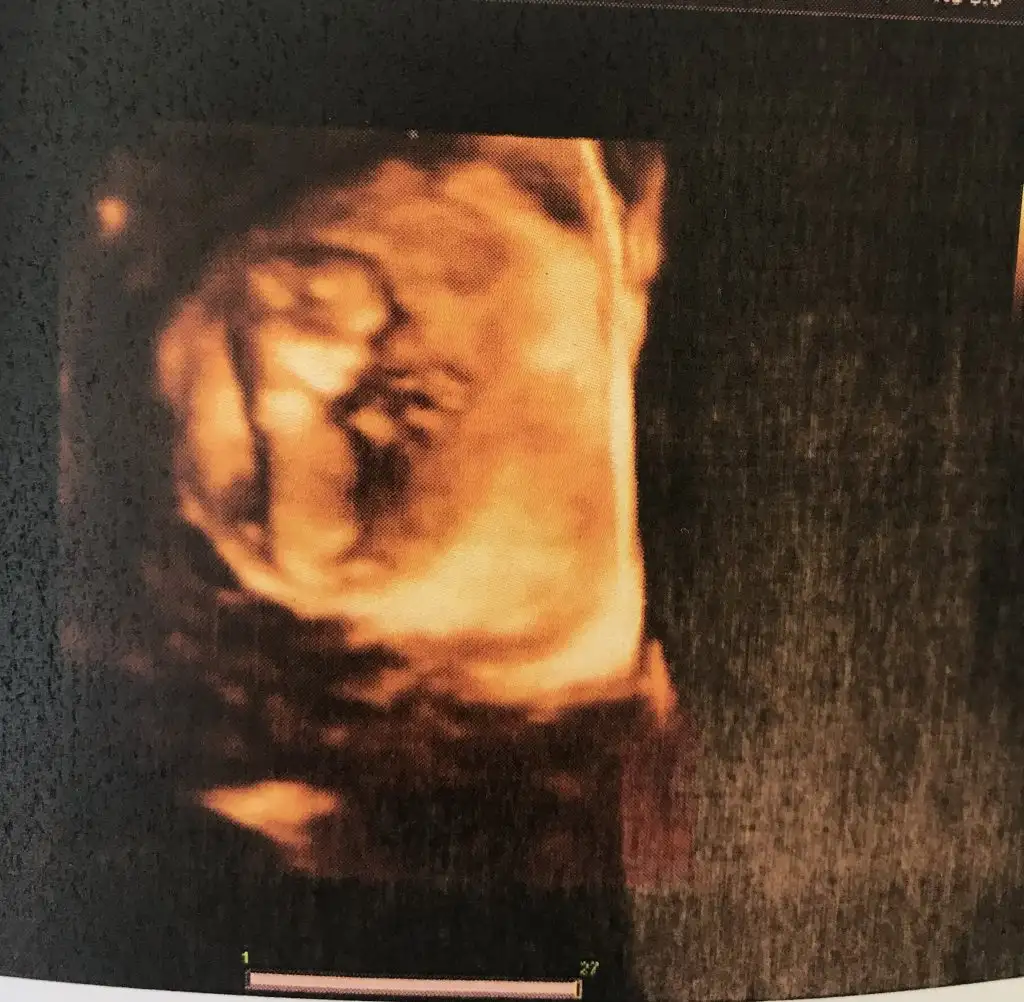

Kızlar tamam artık benim için en büyük adımlar tamamlandı. Cinsiyet sağlık falan. Artık doğum aşamasına geçebiliriz 1 aya falan

Bugün görüş günü gibi olmusKızlar kontrolden çıktım gördük pipiyikız dese çok şaşıracaktım zaten